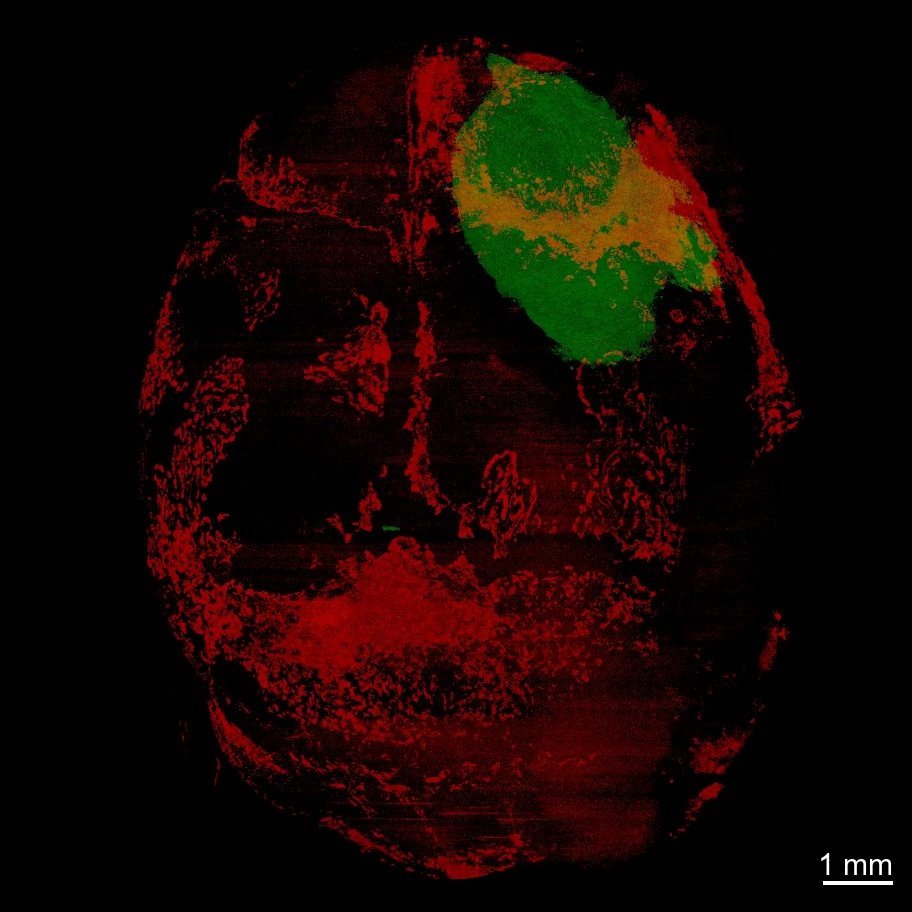

Image credit: Albert Einstein College of Medicine; generated by study co-author Nathaniel Killian

Dr. Behnan and colleagues used advanced imaging techniques on mice that developed two different types of glioblastomas. They found that the tumors caused skull bones to erode, especially along the sutures where skull bones fuse. Such erosions seem to be unique to glioblastoma and other malignant intracranial tumors, since they don’t occur with strokes, other types of brain damage, or even other systemic cancers. Computerized-tomography (CT) images of patients with glioblastoma revealed that decreases in skull thickness were present in the same anatomic areas as in mice.

The skull erosions in the mice were found to have increased the number and diameter of the skull-to-bone channels. The researchers hypothesized that these channels might allow the glioblastoma to transmit signals to the skull marrow that could profoundly change its immune landscape.